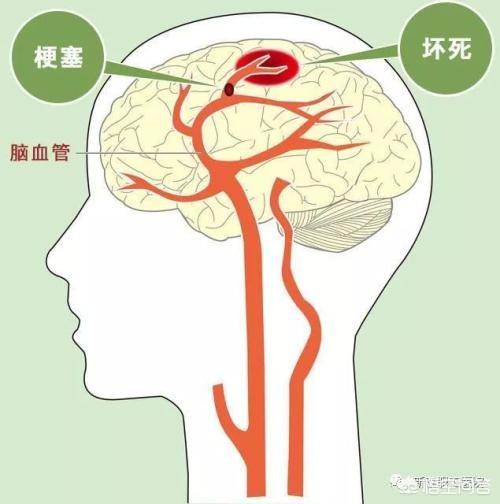

De nombreux ruraux ne reconnaissent pas l'infarctus cérébral. Qu'est-ce que l'infarctus cérébral ? L'infarctus cérébral est une maladie dans laquelle divers emboles sanguins (par exemple, un thrombus fixé à la paroi du cœur, une plaque d'athérosclérose, de la graisse, des cellules tumorales, du fibro-cartilage ou de l'air, etc.) pénètrent dans les artères cérébrales avec le flux sanguin et obstruent les vaisseaux sanguins, provoquant une nécrose ischémique des tissus cérébraux dans la zone desservie par les artères.

Pour simplifier, il s'agit de la nécrose des cellules cérébrales qui se produit lorsque les vaisseaux sanguins du cerveau sont bloqués, provoquant une ischémie cérébrale.

Les accidents vasculaires cérébraux peuvent être divisés en deux catégories : les accidents hémorragiques cérébraux et les accidents ischémiques cérébraux. L'accident vasculaire cérébral ischémique (infarctus cérébral) est le type d'accident vasculaire cérébral le plus courant en Chine.L'accident vasculaire cérébral ischémique est un état dans lequel le flux sanguin vers le cerveau est insuffisant en raison de l'obstruction des vaisseaux sanguins, ce qui entraîne une nécrose ischémique et une perte de fonction des tissus cérébraux, l'embolie cérébrale et la thrombose cérébrale étant les causes les plus courantes. Avant l'apparition de l'AVC ischémique, les patients peuvent présenter des symptômes temporaires d'ischémie cérébrale (communément appelés mini-AVC), notamment l'apparition soudaine d'un engourdissement et d'une faiblesse unilatérale des bras et des jambes, des troubles de l'élocution, une vision floue, une perte d'équilibre, etc.Il s'agit d'un précurseur important de l'accident vasculaire cérébral... Les plaques d'athérome et la sténose des artères carotides cérébrales sont des facteurs importants de l'accident vasculaire cérébral ischémique.Outre les personnes d'âge moyen et les personnes âgées, les patients souffrant d'hypertension artérielle, d'hypercholestérolémie, de diabète sucré et les fumeurs de longue date constituent également les groupes les plus fréquents.

L'infarctus cérébral est principalement causé par la concentration de lipides sanguins dans l'organisme, la formation de caillots sanguins dans les vaisseaux sanguins et le blocage de la circulation sanguine entraînant un infarctus cérébral, l'infarctus cérébral n'est pas au point de causer la mort, mais il y aura une hémiplégie, ou une paralysie, ou même deviendra végétatif, principalement en raison de la compression des nerfs du cerveau causée par la personne.